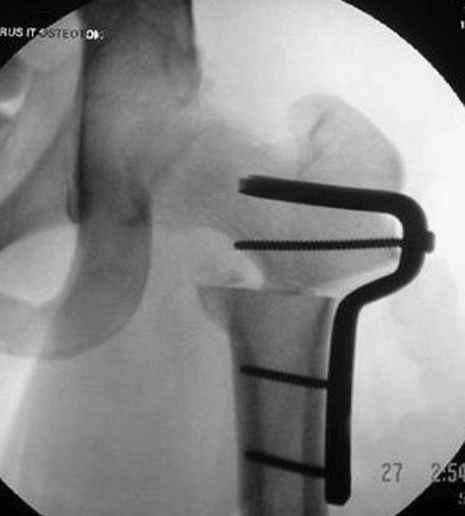

На рисунке N1 предоперационный план лечения ложного сустава шейки бедра- линия ложного сустава, угол и направление введения импланта, клиновидная остеотомия в градусах и миллиметрах, второй снимок после коррекции, расчет, на сколько удлиняется конечность и размеры импланта;

N3 рисунок окончательный снимок, после операции моя рентгенограмма должен выглядеть примерно как эта картина. На N4 снимке клин перед удалением; N5 послеоперации 3 нед.; N6 окончательная рентгенограмма.

(доложен в Ст. Петербурге 2003 и в Москве 2004)

варус при проксимальном отделе 95 градусной пластиной.